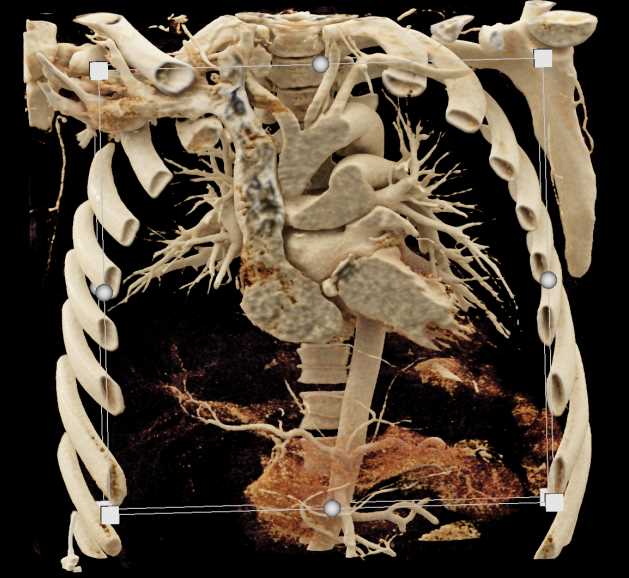

Diagnosis

Aortic Valve Repair